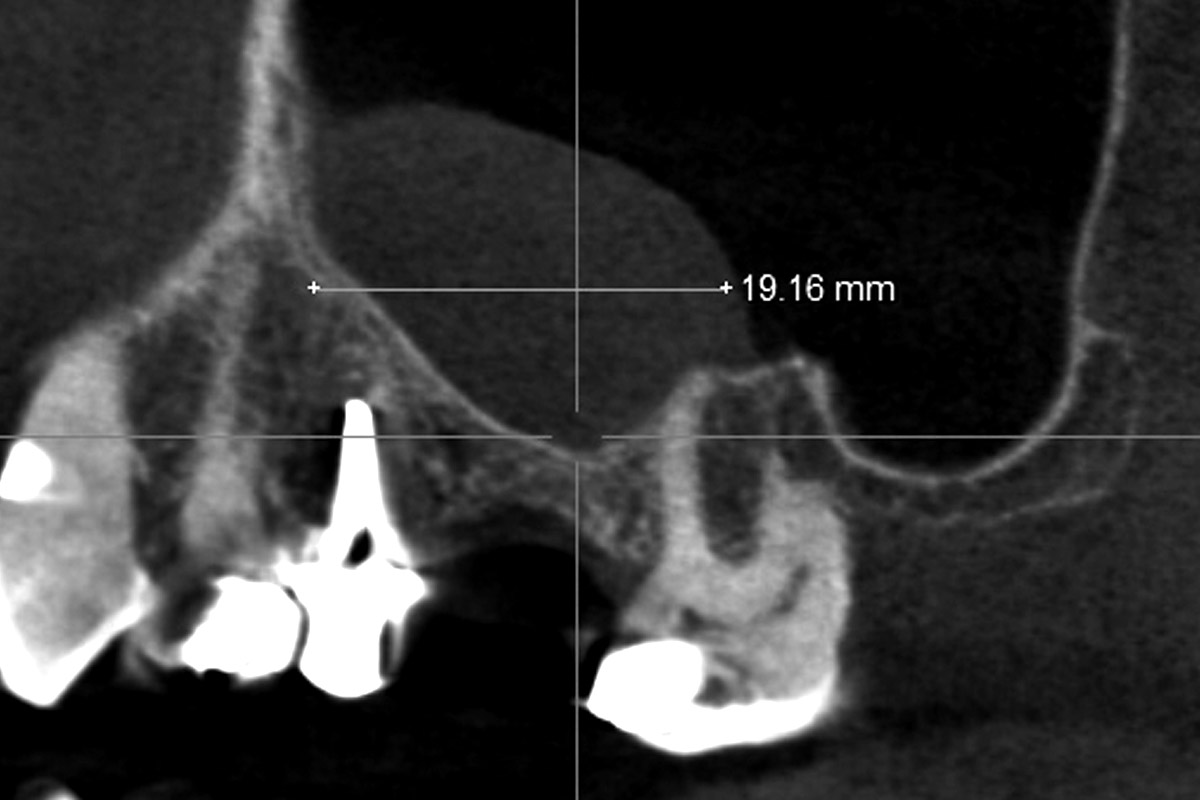

02/35 - CBCT shows maxillary sinus cystMaxillary sinus cyst removal using the Crocodile Technique and subsequent lateral sinus lift - Dres. C. Scognamiglio and A. Perucchi

03/35 - CBCT shows maxillary sinus cystMaxillary sinus cyst removal using the Crocodile Technique and subsequent lateral sinus lift - Dres. C. Scognamiglio and A. Perucchi